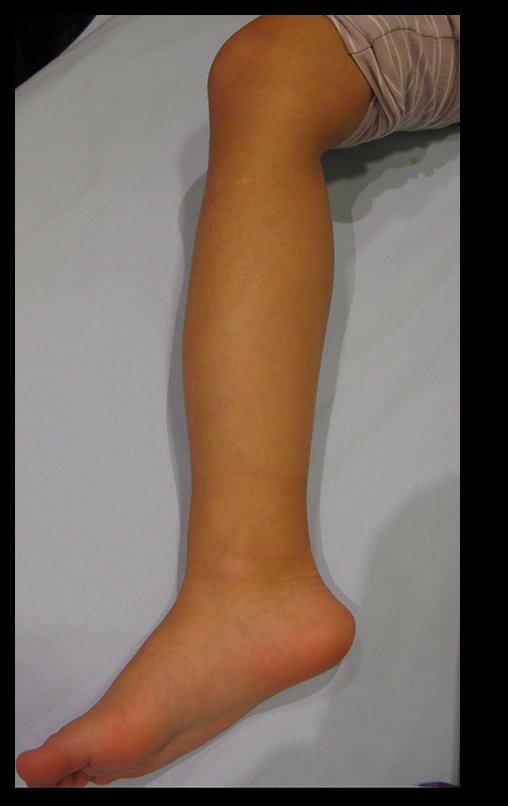

The patient returns to the office six weeks after surgery, figures 100 to 102 and video 1